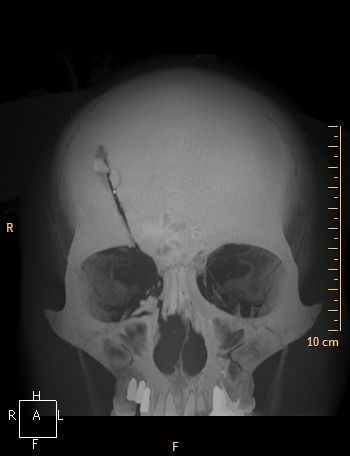

Accident de scie circulaire